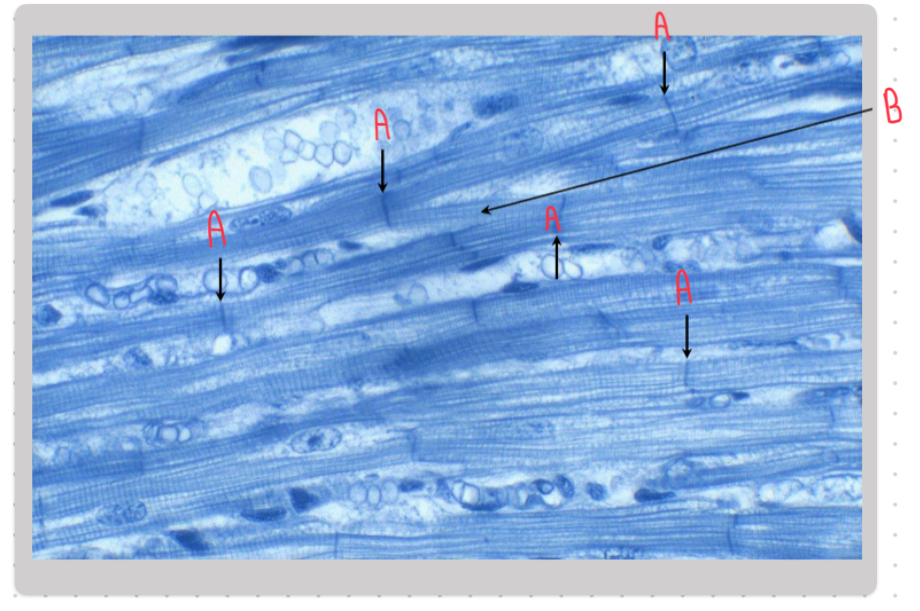

What is the structure labeled A in this image?

The A band

Name the structure labeled B in this image:

The M line.

Name the structure labeled C in this image:

The I band.

Name the structures labeled D in this image:

Z lines.